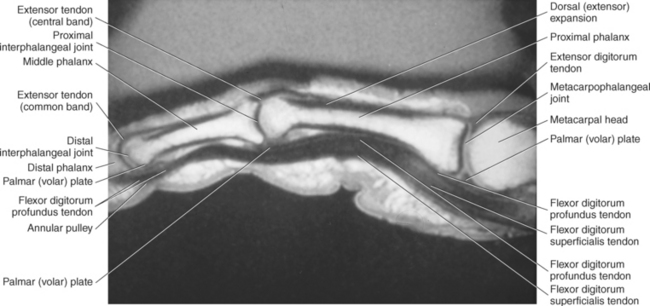

The MCP and interphalangeal joints each have a palmar ligament and two collateral ligaments. The palmar (volar) ligament is a thick, dense fibrocartilaginous tissue that covers the palmar surface of the joints. The palmar ligaments run between and are connected to the collateral ligaments, creating the floor of the interphalangeal and MCP joints. The deep transverse metacarpal ligament (DTML) consists of a series of short ligaments that connect the palmar ligaments of the metacarpal heads (Figure 9.123). The DTML prevents separation of the metacarpals. Along the palmar surface of the fingers, the ligamentous structures of the radial and ulnar collateral ligaments, radial and ulnar accessory collateral ligaments, and palmar plates provide stability for the MCP and interphalangeal joints (Figure 9.121). There is a fibroosseous tunnel along the palmar aspect of each finger for the passage of the flexor tendons. The tunnel is created by well-defined areas of thickening of the tendon sheath and is called the annular pulley system. It is composed of five annular pulleys and three cruciate pulleys, which are important structures that prevent the displacement of the tendons during flexion of the fingers (Figure 9.122). The dorsal surface of the hand and fingers contains the extensor mechanism or extensor hood (Figures 9.123 through 9.126). The extensor hood consists of the digital extensor tendon, extensor hood proper, and insertions of the lumbricals and interossei muscles and serves to maintain the integrity of the extensor tendons along the path of the MCP and interphalangeal joints.

The muscles of the ventral group are demonstrated on Figures 9.97 through 9.99. The flexor digitorum profundus muscle is a long, thick muscle responsible for flexing the distal interphalangeal joints of the fingers. It originates from the anterior surface of the proximal ulna and extends medially to the interosseous membrane. Similar to the flexor digitorum superficialis, the flexor digitorum profundus divides into four tendons before reaching the flexor retinaculum. The four tendons pass deep in the carpal tunnel and continue distally to insert on the distal phalanges, where they pair up with the flexor digitorum superficialis to provide flexion of the middle and proximal phalanges of the second through fifth digits (Figure 9.99, B).

The flexor digitorum superficialis muscle is the largest muscle of the superficial muscles in the forearm. It arises from three heads: the humeral head from the common flexor tendon, the ulnar head from the coronoid process, and the radial head from the anterior surface of the proximal half of the radius. Just before reaching the flexor retinaculum, the muscle divides into four tendons that share a common synovial sheath through the carpal tunnel. After passing under the flexor retinaculum, the tendons insert on the lateral sides of the middle phalanges of the second to fifth digits. The flexor digitorum superficialis is a strong flexor of the middle and proximal phalanges of the second through fifth digits (Figure 9.86).